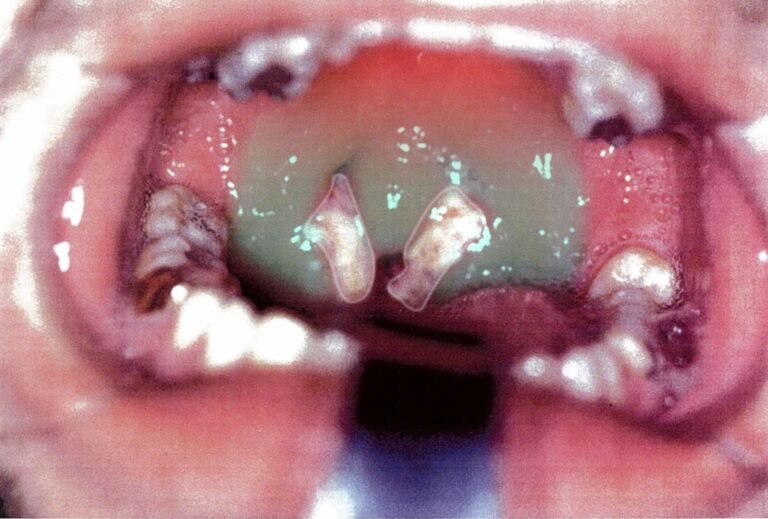

- Pharyngeal inflammation: Tonsillar exudates, pharyngeal erythema

- Palatal petechiae: Supportive but not pathognomonic